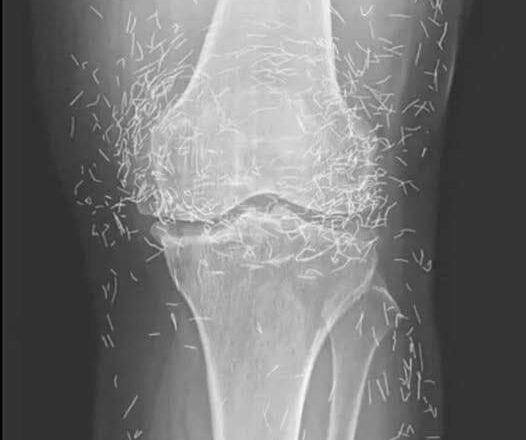

Years later, when doctors took X-rays to evaluate her knee condition, they weren’t prepared for what appeared on the images. Her knees were filled with dozens of bright, metallic flecks — tiny needles embedded deep within the joint area.

The findings were later documented in a case published by the New England Journal of Medicine.

Beyond inflammation, the needles created another problem: imaging complications. Metal objects can obscure parts of the anatomy on X-rays, making it harder for doctors to clearly assess joint damage or disease progression.

Even more concerning, the presence of metal inside the body can make certain scans dangerous. MRI machines rely on powerful magnetic fields, and embedded needles may shift during scanning, potentially damaging blood vessels or surrounding tissue. In short, future diagnostic options for this patient became limited.